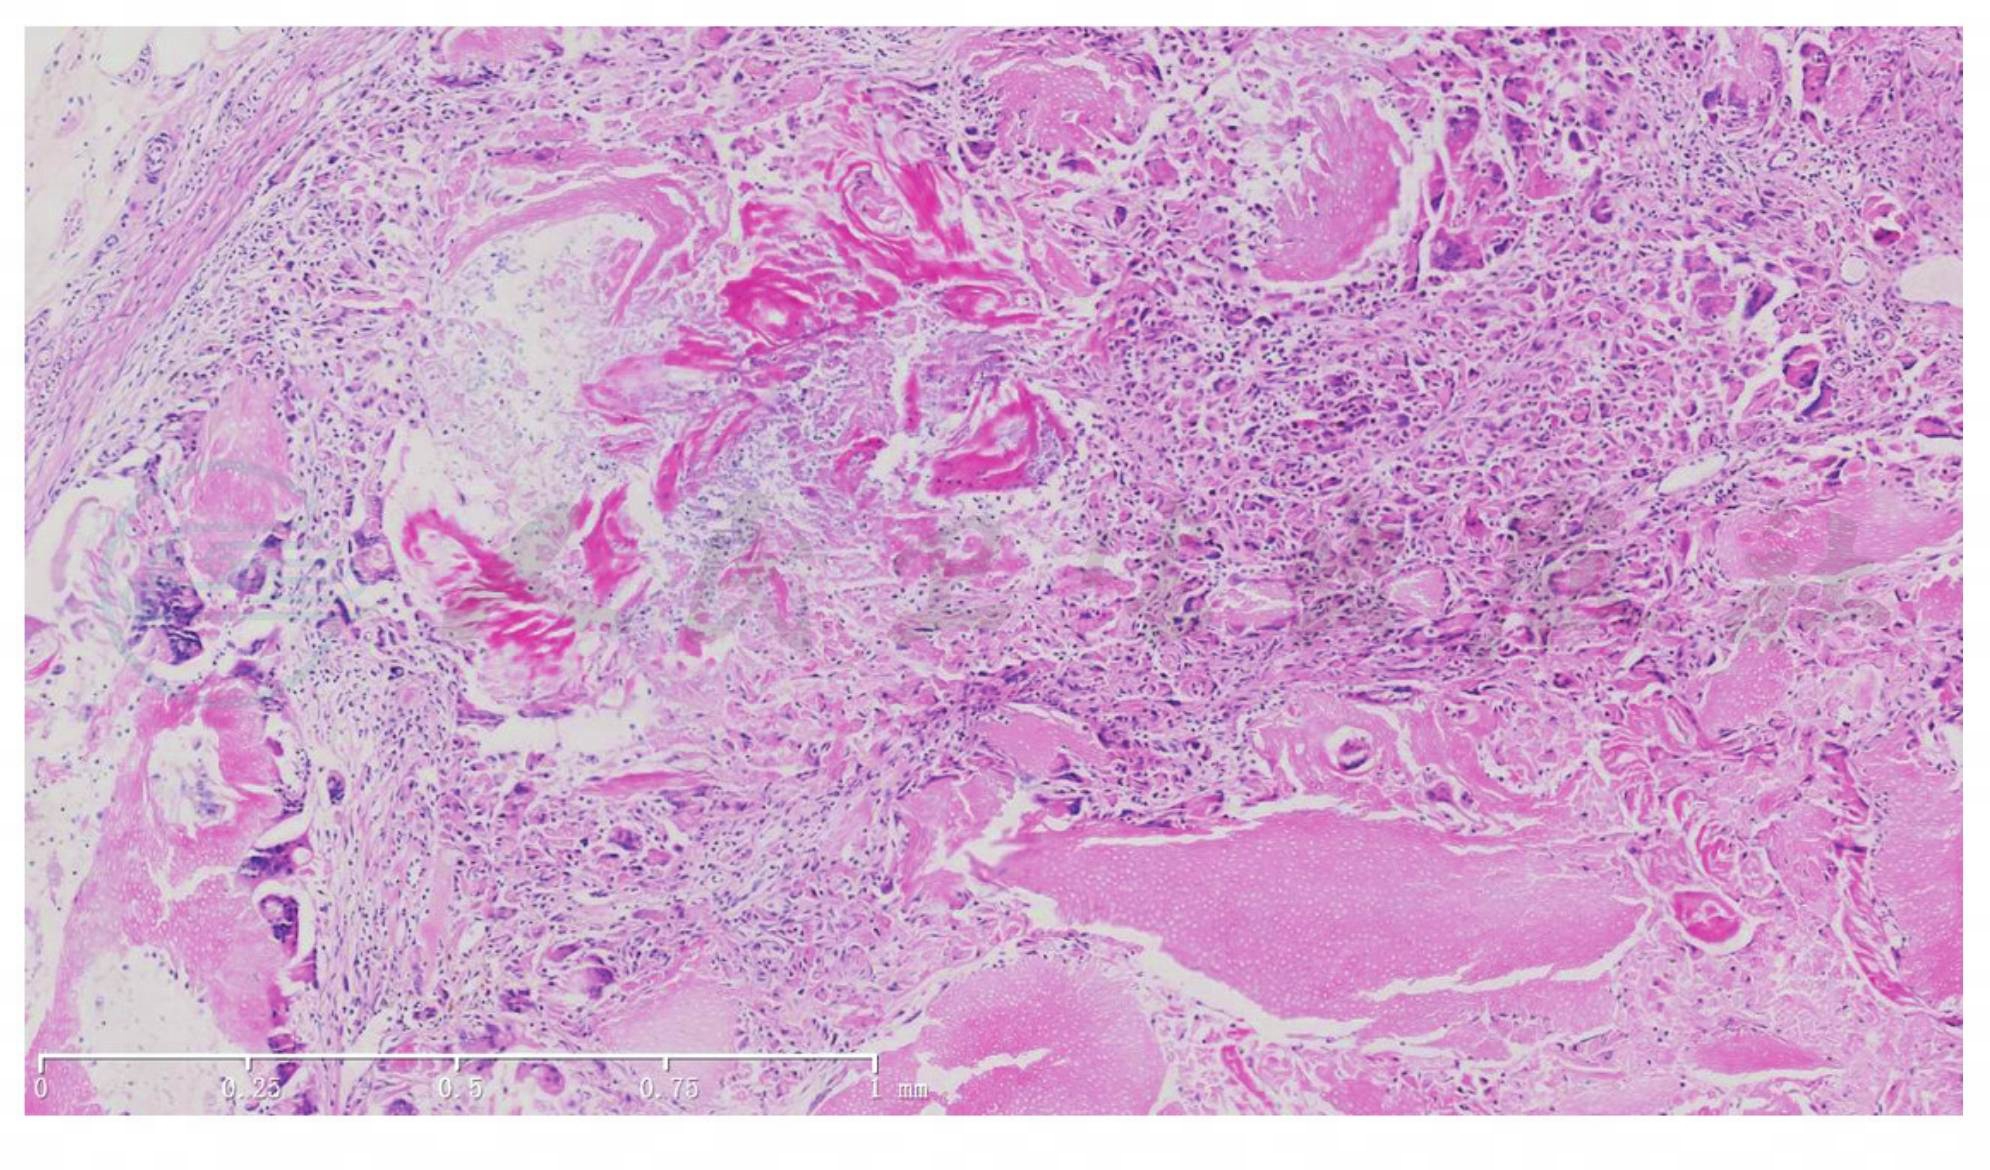

早期皮损显示明显的有丝分裂活性,但无病理性核分裂,表示皮损处于快速生长阶段,而无恶变倾向。随着肿瘤的成熟,基底样细胞转化为影细胞,胞质呈强嗜酸性,核变小,染色质丰富。最后,核仁消失,有片状密集嗜酸性角蛋白碎片残留,其中影细胞轮廓模糊不清,常见巨细胞。

角化主要发生于毛发,但有时可见点状表皮角化灶。某些肿瘤存在另一特征性改变,其基底样细胞及间质内组织细胞内常见黑素颗粒。80%的皮损区域有钙盐沉积,成熟区域中更为常见。病变中常见影细胞的嗜碱性颗粒,偶见钙化大团块,20%的患者会发生骨化现象。

图3毛母质瘤。显示多核巨细胞、影细胞及嗜碱性团块(HE染色,×40)